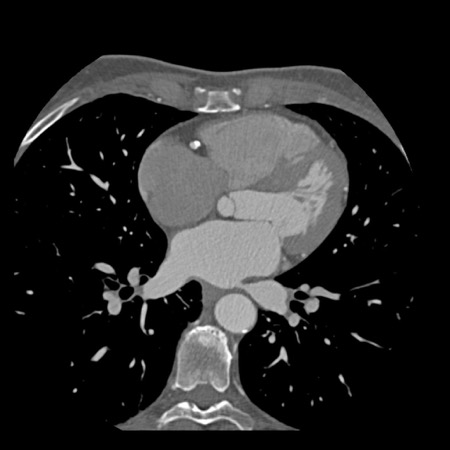

Modifier S – stent

The presence of a stent is indicated by modifier “S”.

Examples

- If a patient has a stent, showing no in-stent restenosis and a mild

(25-49%) stenosis in the coronaries, this patient classifies as CAD-RADS

2/S. - Similarly, a patient with no in-stent restenosis but severe (70-99%)

stenosis in a coronary other than LM classifies as CAD-RADS 4A/S. - If there is a severe (70-99%) in-stent restenosis in a coronary other

than LM, this patient classifies as CAD-RADS 4A/S. - If the stent is non-diagnostic and there is no >49% stenosis present

in the coronaries, the patient classifies as CAD-RADS N/S.

Note: the location of the stenosis does not matter, when using

CAD-RADS.

What matters is that the patient has a severe stenosis and needs further

management.

Please note: total coronary plaque burden should also be added and is

placed before the modifier S.